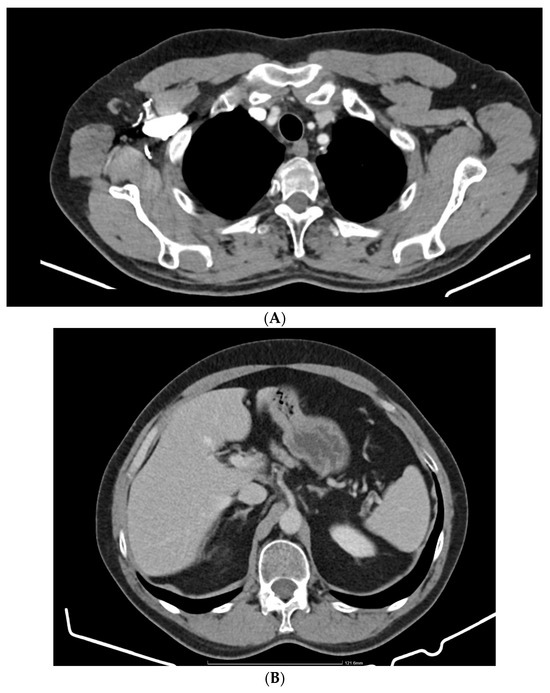

2. Case Report